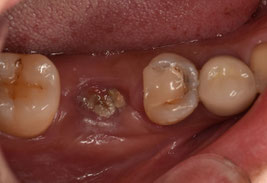

ヨーロッパの先進国で根管治療を受けることができず、日本での治療を希望された方の症例です。

「日本よりも素晴らしい医療を受けることができそうなヨーロッパの国」から来院された方です。在住先の複数の歯科医院で右下5番の根管治療を断られたため、日本での治療を希望され来院されました。

右下6番も根管治療を断られてしまい、痛みが酷かったため抜歯したそうです。抜歯してからも強い違和感と腫れが続いているそうです。前医で撮影したレントゲンデータをもとに、処置を進めることとしました。

先生だったらこの写真で右下5番を抜歯判定しますか?どう考えても、まずは保存を第一選択とするはずです。しかし、先進的な国であればあるほど、皮肉にも抜歯になってしまうのです。

広範囲に軟化象牙質を認めましたが、歯肉縁上に十分な健全歯質を保存できたため、根管治療を施術しました。前医での複数枚のレントゲン写真があったため、そちらを参考に処置を進めました。